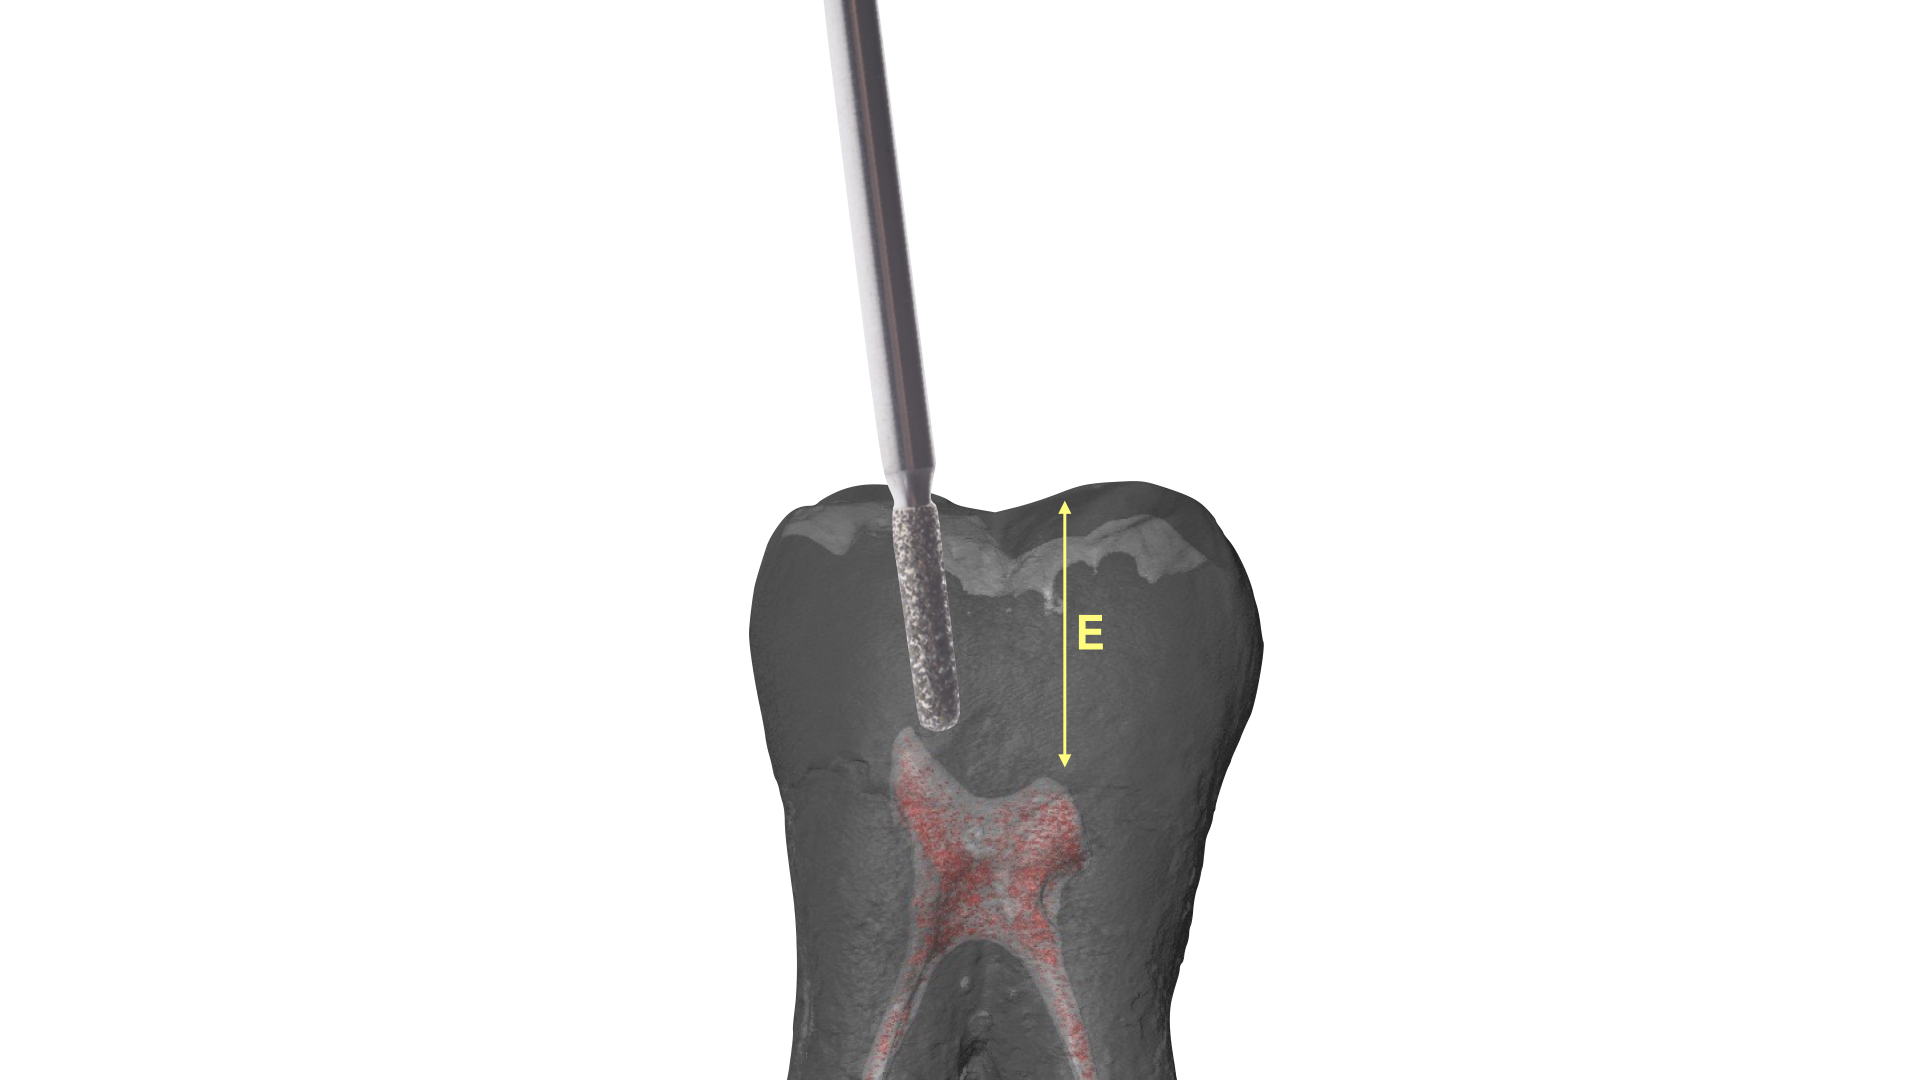

La fresa che ci guida in questo step ha una parte lavorante di 6 mm (Komet 880-314-012) che, ricordando una delle regole di Deutsch, non dovrà penetrare oltre il nostro punto di repere occlusale: diventerebbe alto il rischio di sovra estendere la preparazione e di indebolire se non di perforare il pavimento (Figura 14).

La parte diamantata della fresa è la nostra guida, lo stop oltre il quale è sconsigliato procedere nei molari superiori e inferiori.

Un altro motivo che suggerisce di utilizzare una fresa cilindrica a testa arrotondata è la possibilità di tracciare in modo netto, riproducibile e conservativo un disegno cavitario sulla superficie occlusale e contestualmente di approfondirsi in direzione apicale rispettando un asse lineare. La testa arrotondata riduce notevolmente il rischio di lasciare solchi angolati molto netti in prossimità del pavimento pulpare: il disegno risulterà molto più addolcito e saranno evitati inutili sacrifici di tessuto dentale sano.